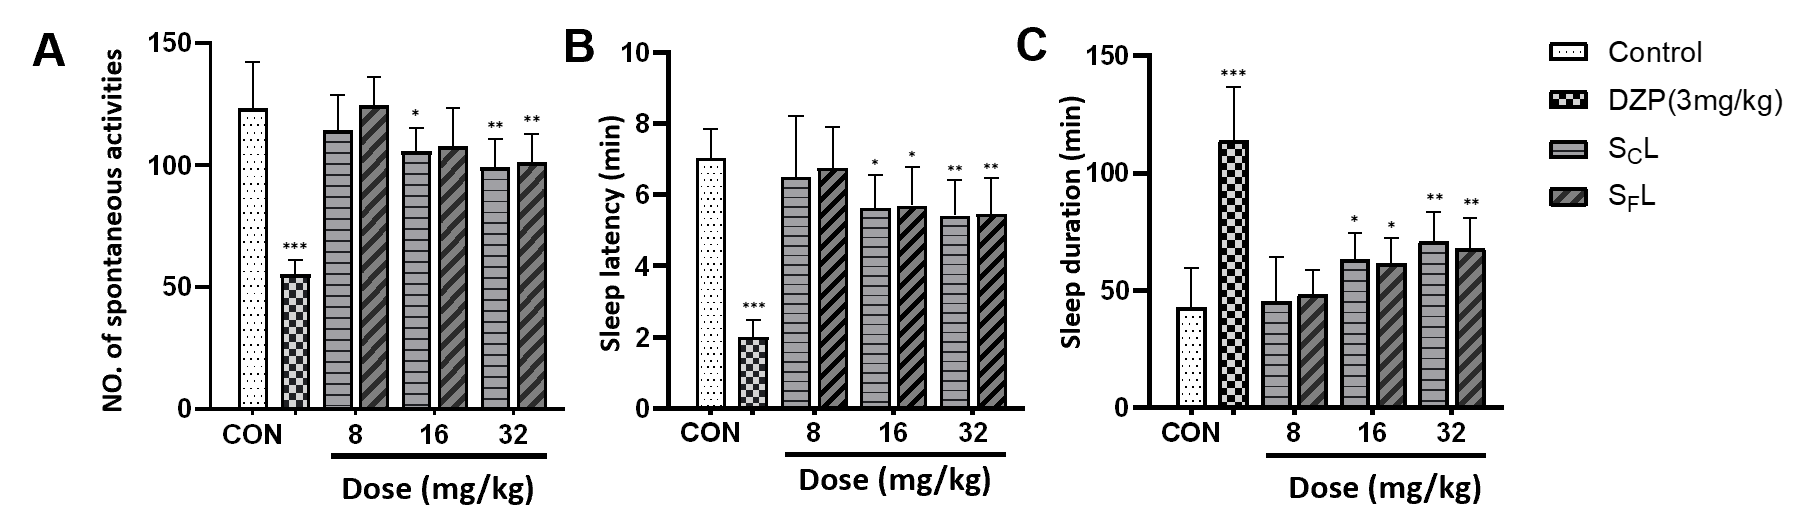

尽管SCL和SFL在民间长期用于改善失眠,但其镇静催眠作用缺乏系统研究支持。本研究通过自发活动实验、戊巴比妥钠诱导睡眠实验、对氯苯丙氨酸失眠模型实验及氟马西尼逆转催眠实验,综合评价了二者的镇静催眠活性。结果表明,SCL和SFL均以剂量依赖方式增强戊巴比妥的睡眠效应(图2)、改善氯苯丙氨酸(pCPA)所致的失眠状态(图3),且SCL的效果显著优于SFL。氟马西尼可抑制两者的催眠作用(图3),同时,SCL与SFL均与5-HTP表现出协同催眠效应(图3),表明5-HT与GABA系统共同介导其镇静催眠活性。

图2 SCL和SFL对小鼠自发活动数(A)、戊巴比妥催眠诱导小鼠睡眠潜伏期(B)和持续时间(C)的影响(与对照组比较,*p< 0.05,**p< 0.01,***p< 0.001;与模型组比较,#p< 0.05,##p< 0.01,###p< 0.001)